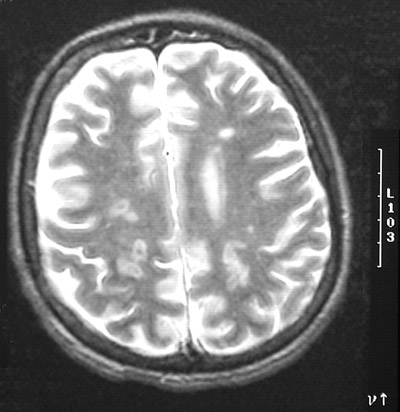

| The axial T2 weighted MRI scan above and the axial FLAIR MRI scan below, both of the cerebrum, reveal multiple bright embolic infarcts in a patient with infective endocarditis of mitral and aortic valves. Since the emboli may not completely occlude the vessel, there can be hemorrhage into the infarct. |